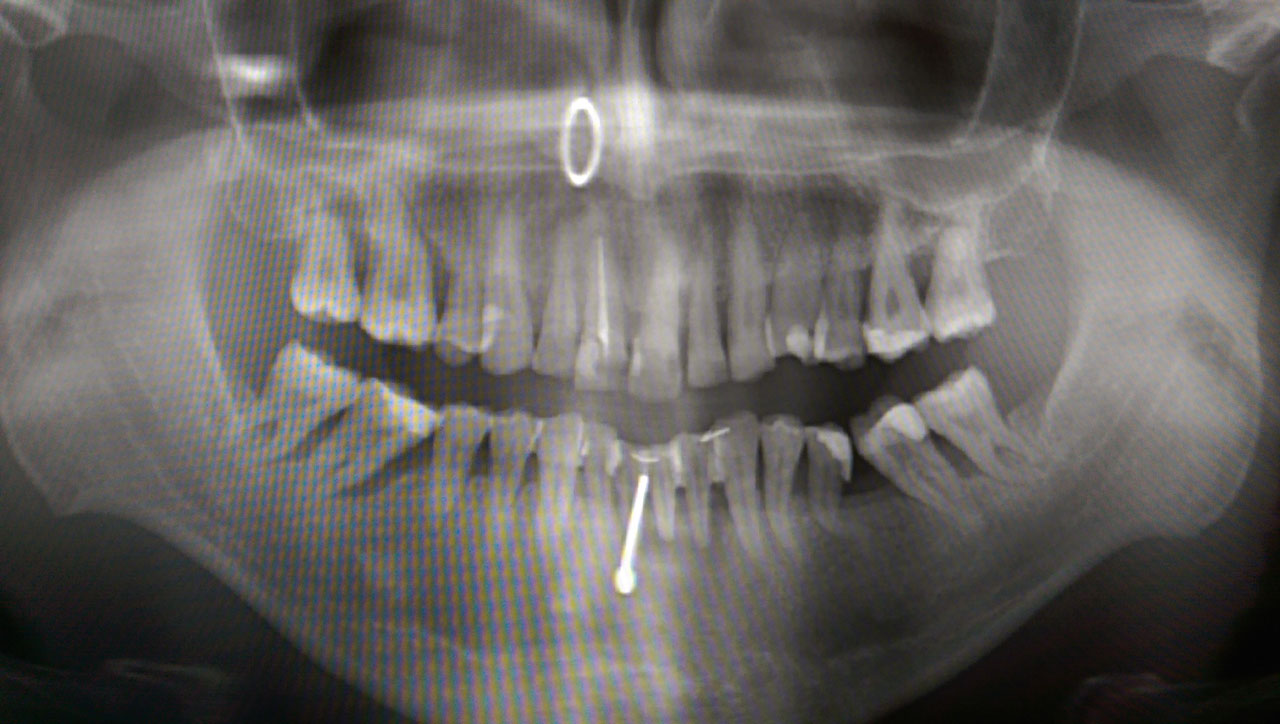

Teljes fogatlanság helyreállítása 2 nap alatt

Teljes fogatlanság helyreállítása 2 nap alatt azonnal terhelhető svájci IHDE implantátumokkal és PMMA műanyag hidakkal. Intraorális szkennerrel vettünk lenyomatot az implantáció után, és erre a digitális mintára készítette el a fogtechnika a hidak digitális tervezését, majd faragta ki műanyagból. Ezt a gyors munkát az azonnal terhelhető implantátumok és a digitális lenyomat, tervezés segítségével tudtuk megcsinálni mindössze 2 nap alatt. Dr. Kelemen Péter és a Symbion Fogtechnika munkája.